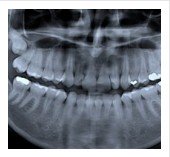

Wisdom Tooth Extraction Royse City

Wisdom teeth extraction surgery is often performed to prevent future

dental issues or to correct an existing problem. Around the age of 18,

adults have 32 teeth, 16 on top and 16 on bottom and yet the average

mouth can only hold 28 teeth. Dental complications can arise when the

four extra teeth, known as the Third Molars, or “wisdom teeth” erupt,

forcing their way into the space.